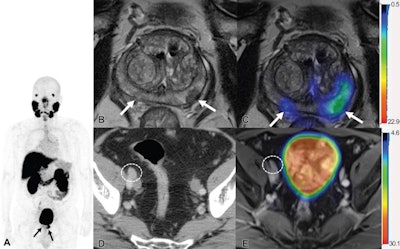

Images show F-18 DCFPyL PET/MRI and contrast-enhanced CT in a 65-year-old man with clinical T3 stage prostate cancer who underwent bone scintigraphy with negative findings (not shown). (A) Anteroposterior maximum intensity projection image of F-18 DCFPyL PET/MRI shows PSMA-avid primary tumor (arrows). (B) Axial T2-weighted MRI of the prostate and (C) corresponding fused F-18 DCFPyL PET/MRI in the prostate show multifocal PSMA-avid primary tumors involving bilateral peripheral zone of the gland (arrows). (D) Axial CT image shows a 1.1-cm right external iliac lymph node, suspicious for nodal metastasis, by size criteria (N1; circle). (E) Axial fused F-18 DCFPyL PET/MRI does not show corresponding increased tracer activity (N0; circle). At time of radical prostatectomy, lymph node sampling was negative for metastases (pT3a pN0). Image courtesy of Radiology.The authors noted that treatment change after PET in this study was similar to that seen in a multicenter randomized trial of gallium-68 (Ga-68) PSMA-11 PET/CT in prostate cancer patients, compared with conventional imaging. Ga-68 PSMA-11 received U.S. approval for imaging in prostate cancer patients in December 2020, and it was the first PSMA tracer to achieve the mark.